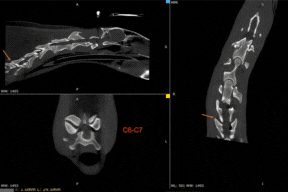

The Equina by Asto CT is the world’s only bi-axial equine standing CT scanner that scans vertically for limb pairs and horizontally for the head and neck. The ability to scan a standing sedated horse eliminates the need for general anesthesia.